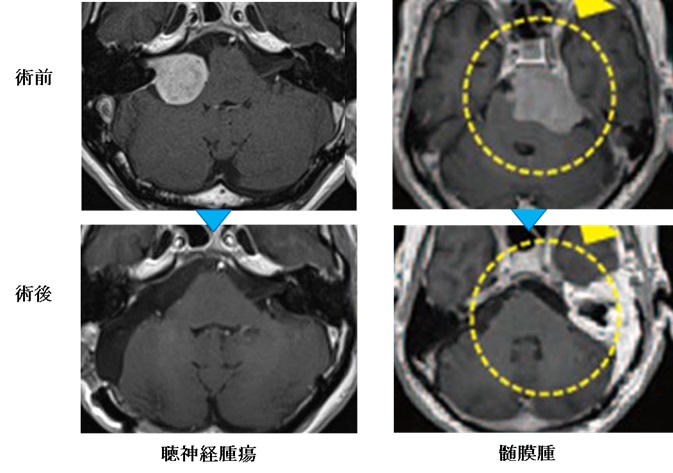

頭蓋底手術の基礎を学ぶための実践的なガイド。- タイトル: 入門 頭蓋底手術- 著者: Tetsuro Sameshima, M.D., Ph.D.- 言語: 日本語- 出版社: MEDICAL VIEW- 内容: Microanatomy and Dissection of the Temporal Bone for Beginnersご覧いただきありがとうございます。